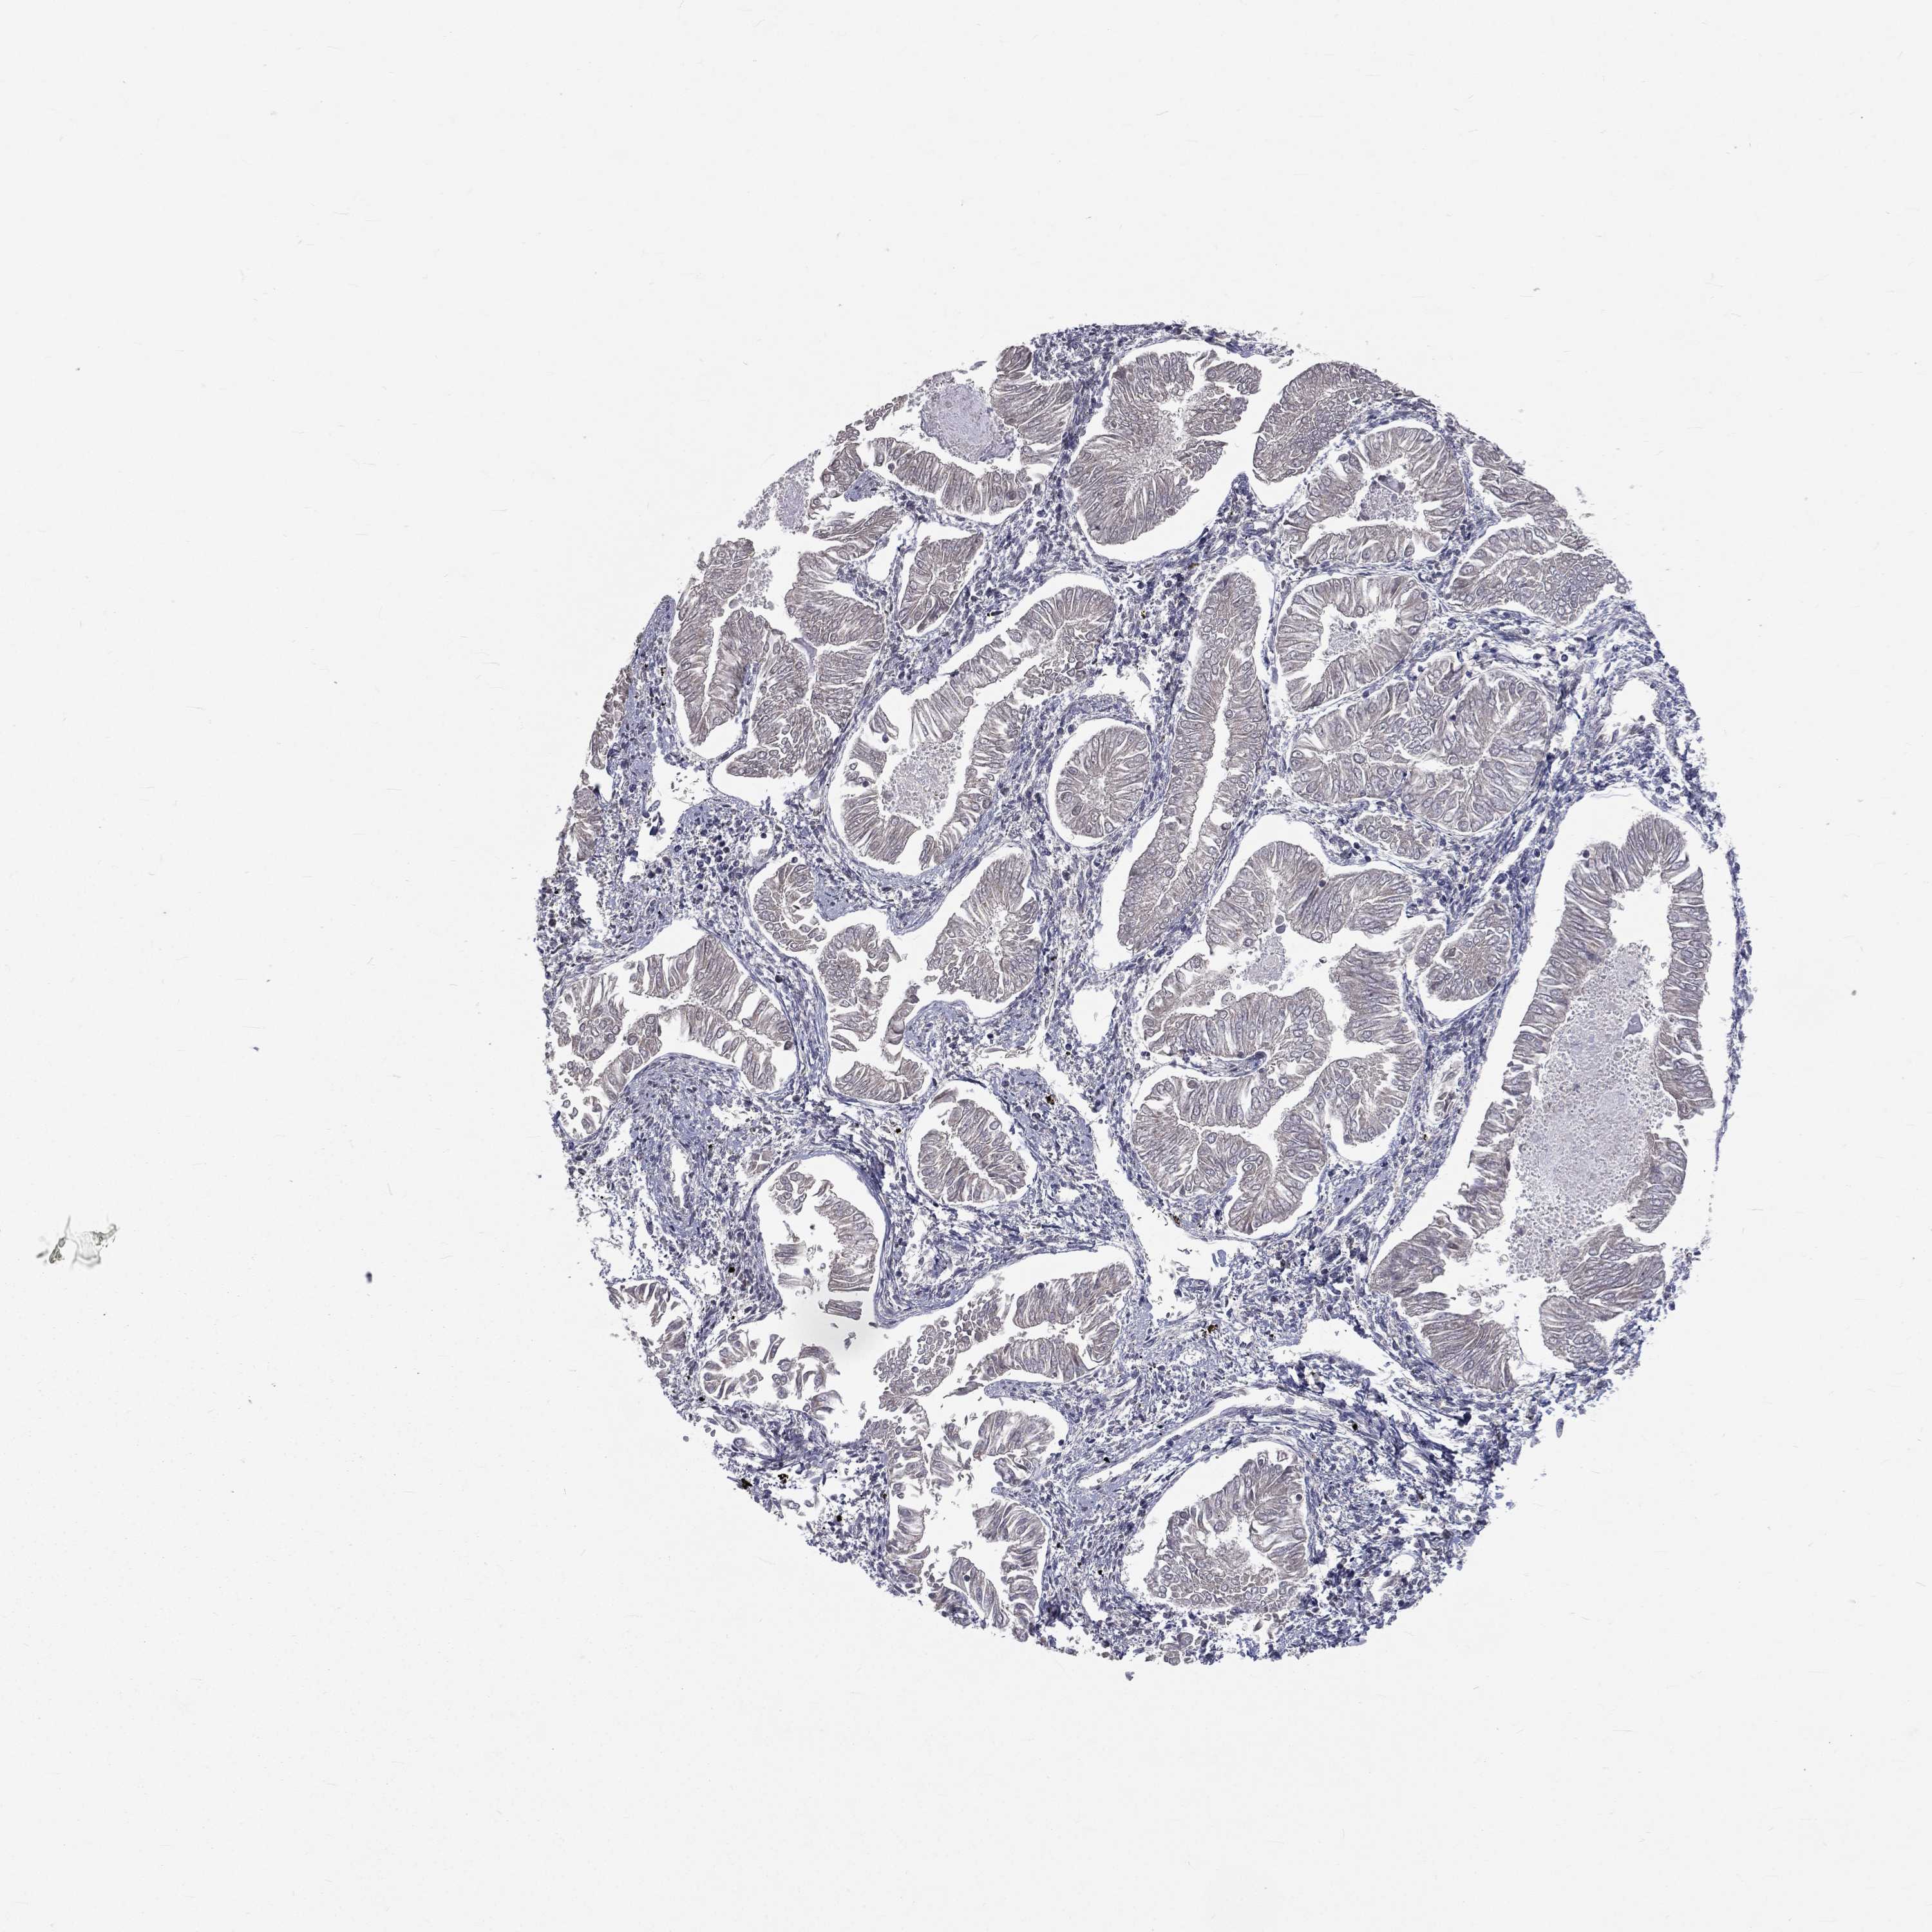

ENDOMETRIAL CANCER - Protein expressioni

A mouse-over function shows sample information and annotation data. Click on an image to view it in a full screen mode. Samples can be filtered based on level of antibody staining by selecting one or several of the following categories: high, medium, low and not detected. The assay and annotation is described here.

Note that samples used for immunohistochemistry by the Human Protein Atlas do not correspond to samples in the TCGA dataset.

Antibody stainingi

Antibody staining in the annotated cell types in the current human tissue is reported as not detected, low, medium, or high, based on conventional immunohistochemistry profiling in selected tissues. This score is based on the combination of the staining intensity and fraction of stained cells.

Each image is clickable and will lead to virtual microscopy that enables deeper exploration of all samples and also displays staining intensity scores, fraction scores and subcellular localization as well as patient and tissue information for each sample.

Antibody HPA044620

Antibody HPA058621

Staining

High

Medium

Low

Not detected

Intensity

Strong

Moderate

Weak

Negative

Quantity

>75%

75%-25%

<25%

None

Location

Nuclear

Cytoplasmic/membranous

Cytoplasmic/membranous,nuclear

Adenocarcinoma, NOS